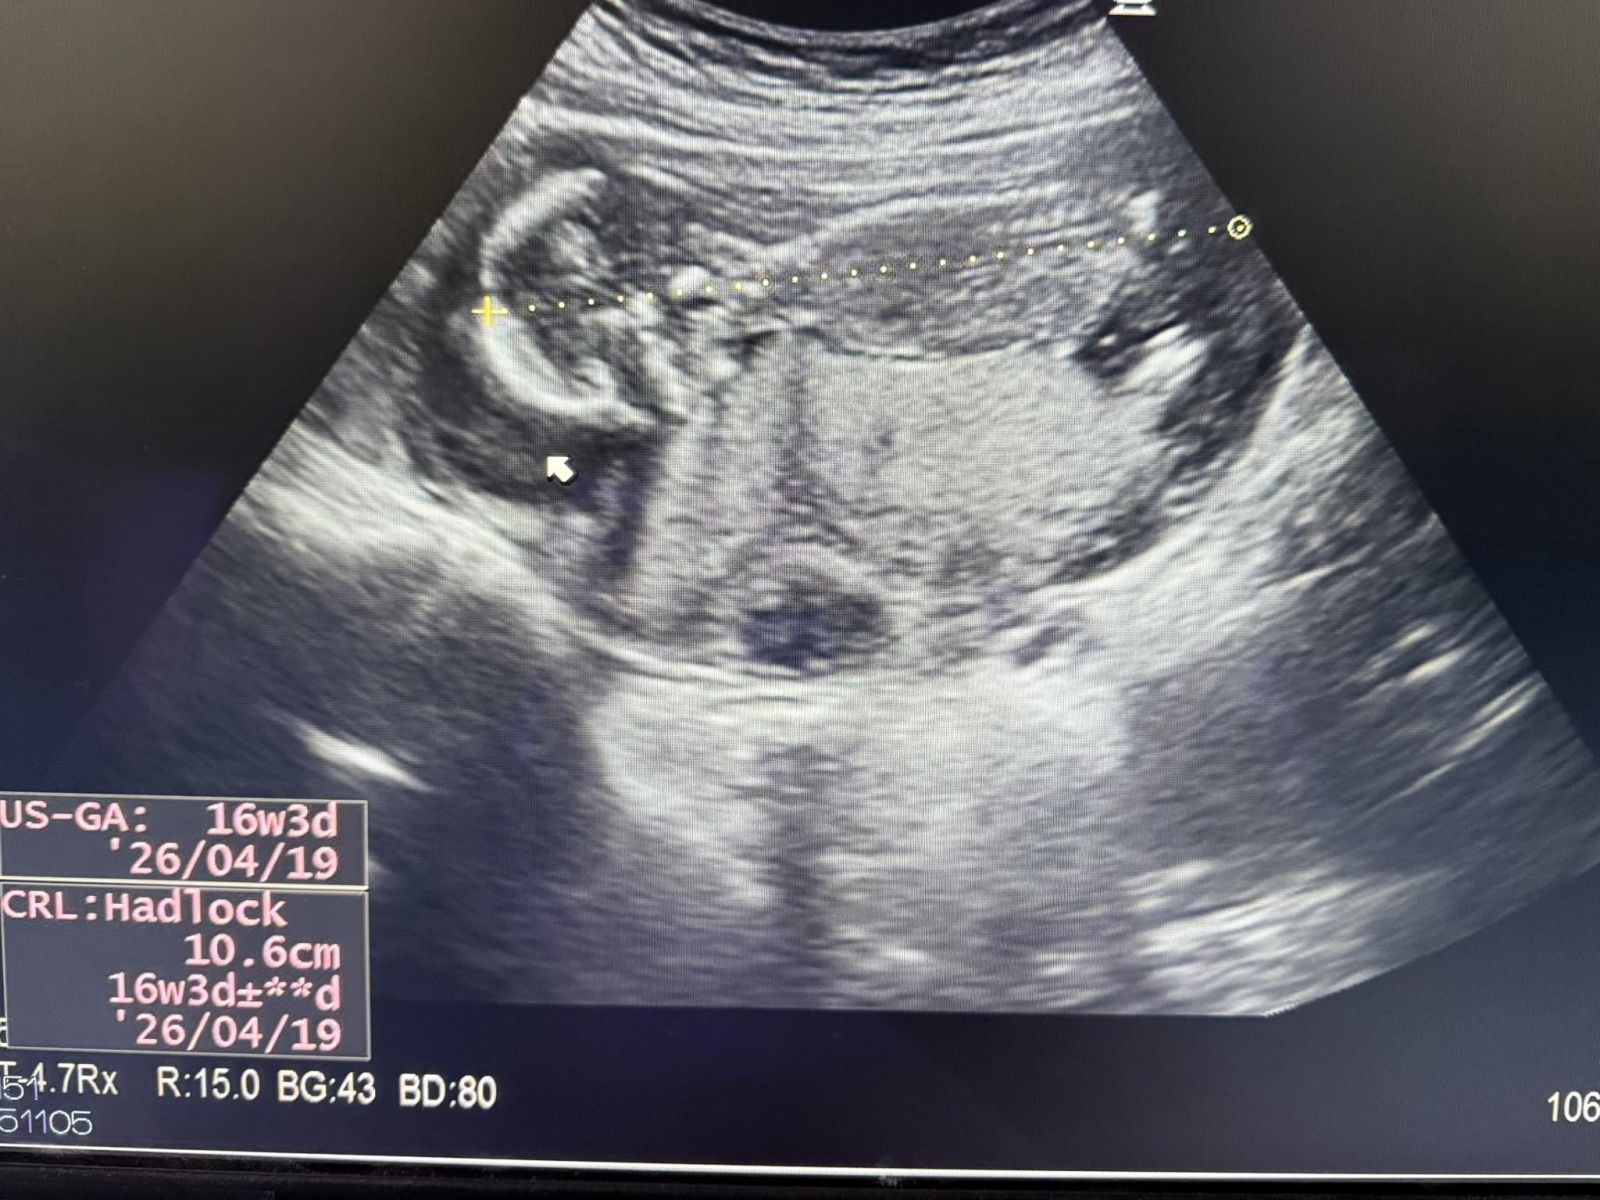

- Currently 16 weeks pregnant, preparing for amniocentesis